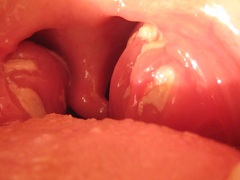

Инфекционный мононуклеоз у детей в 85% случаев сопровождается налетом на носоглоточных и небных миндалинах. Как правило, появление данного симптома (в самом начале или на 3-4 день болезни) вызывает еще большее повышение температуры и ухудшение общего состояния.